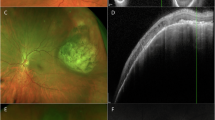

Providers were invited to participate in a survey assessing ability to identify risk factors for small choroidal melanocytic lesion growth to melanoma using either fundus imaging or multimodal imaging. Risk factors included thickness >2 mm on ultrasonography, subretinal fluid on optical coherence tomography, presence of orange pigment by autofluorescence, acoustic hollowness by ultrasonography, and diameter >5 mm by fundus imaging. Performance was assessed before and after reviewing an educational PowerPoint providing pictorial examples of risk factors. Comparison between groups was conducted using two-tailed Fisher’s exact test.

Use of multimodal imaging may be more beneficial than education itself to improve accuracy of risk factor identification for small choroidal melanocytic lesions.